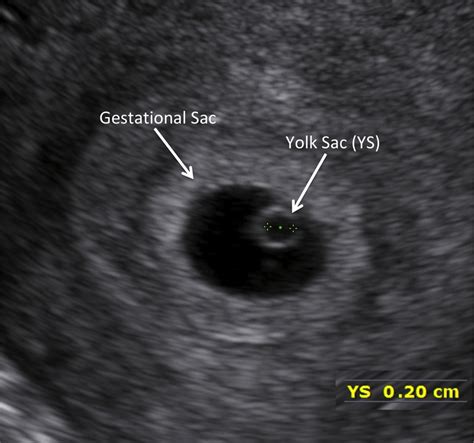

Webaug 11, 2023 · gestational sac evaluation is typically performed between 5 to 7 weeks of gestation. During this period, the gestational sac becomes visible on ultrasound imaging,. Webmar 15, 2024 · what does an empty gestational sac mean? A yolk sac, which indicates a viable pregnancy, is usually seen within the gestational sac by 35 days gestation. Webfeb 26, 2024 · gestational sac, also known as an empty sac pregnancy, blighted ovum, or anembryonic pregnancy, is a condition where the pregnancy sac develops in the uterus.

Ultrasound scans can detect a fetal heartbeat at approximately. Webjun 3, 2016 · i am supposed to be seven weeks along and at my ultrasound yesterday (thursday) all they saw was an empty gestational sac that measured 6 weeks, 5 days. Webjun 25, 2022 · at the ultrasound yesterday the sac was empty. The hcg is around 10k, which is consistent with early 7th week. I will repeat it on monday. But this gives me.